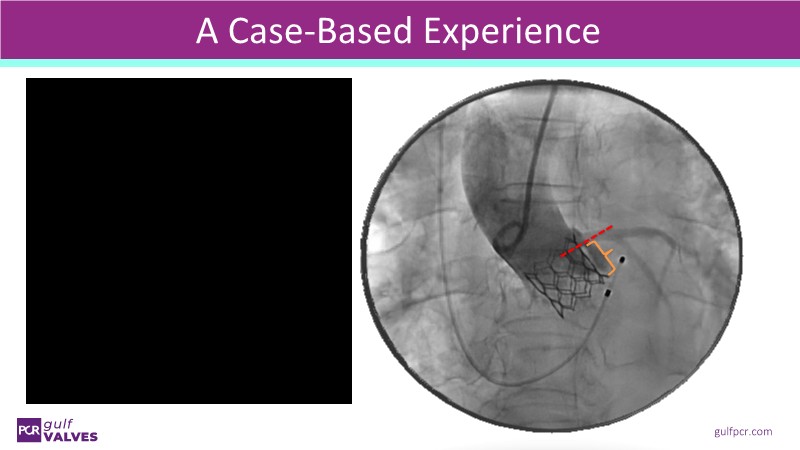

Join this comprehensive session to explore the Myval transcatheter heart valve series, featuring the latest clinical updates from two large randomized controlled trials—Landmark and Compare TAVI. Learn from real-world experiences, including recorded cases, and understand how these innovations translate to complex patient demographics in daily TAVI practice.

- To learn from the best-in-class TAVI practice